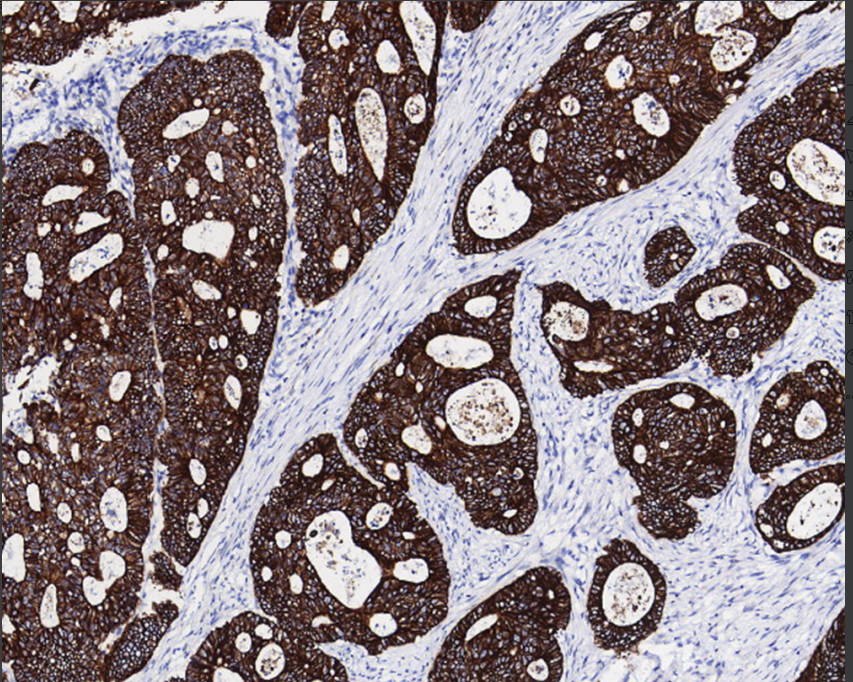

Positive control: Gastric adenocarcinoma/stem cell carcinoma

In normal tissues, CK8 is expressed in almost all non-squamous epithelium, such as colon, stomach, small intestine, tracheal epithelium and migratory epithelium, and is also expressed positively in malignant tumors, such as ovarian cancer, adenocarcinoma of gastrointestinal tract, adenocarcinoma of thyroid gland, ductal carcinoma of mammary gland, neuroendocrine tumors, hepatocellular carcinoma and renal tumors. It is mainly used to diagnose cancer of epithelial origin and metastatic malignant tumors.

CK8 antibody reagents can specifically bind to CK8 molecular antigens. Immunohistochemistry kits containing CK8 antibody reagents are suitable for the auxiliary diagnosis of epithelial-derived cancers and metastatic malignant tumors.